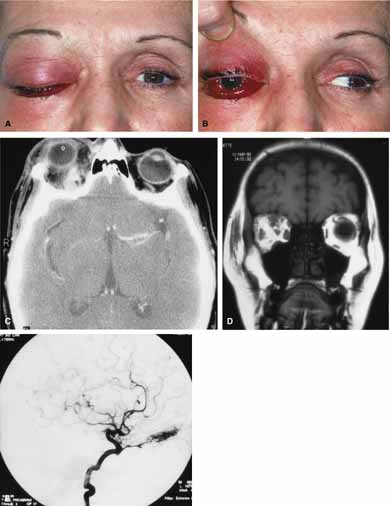

Cartoid cavernous sinus fistula (CCSF) is the most common arteriovenous malformation affecting the orbit and involves abnormal communication between a branch of the carotid artery and the cavernous sinus.79 The resulting high-flow fistula can produce proptosis (may be pulsatile), pain, engorgement of epibulbar veins (corkscrew configurations), limited extraocular motility, raised intraocular pressure and loss of vision (Fig. 12A and 12B). In many cases a bruit may be heard by the patient or examiner. The clinical features may mimic acute thyroid disease, but in contrast to thyroid eye disease, fistulas are usually unilateral. Seventy-five percent of fistulas occur as a result of head trauma; the rest occur spontaneously.79,80 Traumatic causes include head injury (penetrating or nonpenetrating) as well as iatrogenic causes including complications of carotid endarterectomy surgery. The spontaneous fistulas often occur in post-menopausal women. They may be the result of a congenital malformation (e.g., aneurysm or arteriovenous malformation) or associated with atherosclerotic changes, hypertension, collagen vascular disease, or childbirth. Some cases remain idiopathic. The spontaneous fistulas tend to be low-flow shunts in contrast to high-flow traumatic fistulas. Carotid cavernous fistulas can be subdivided as: (1) etiologic (spontaneous or traumatic); (2) hemodynamic (high or low flow), and 3) anatomic (direct or dural).79,80 CT and MRI are useful screening tests and may show dilation of the superior ophthalmic vein, increased extraocular muscle size and enlargement of the cavernous sinus (Fig. 12C and 12D). The definitive diagnostic test is bilateral selective internal and external carotid angiography.

Fig. 12 A. A 68-year-old female developed sudden proptosis (over 2–3 minutes), decreased vision, conjuntival injection, chemosis, and restricted motility. B. Multiple corkscrew vessels are seen secondary to engorgement of the epibulbar vessels. C. Axial computed tomography (CT) scan revealed proptosis and enlargement of the extraocular muscles. D. Axial computed tomography (CT) scan also revealed an enlarged superior ophthalmic vein.